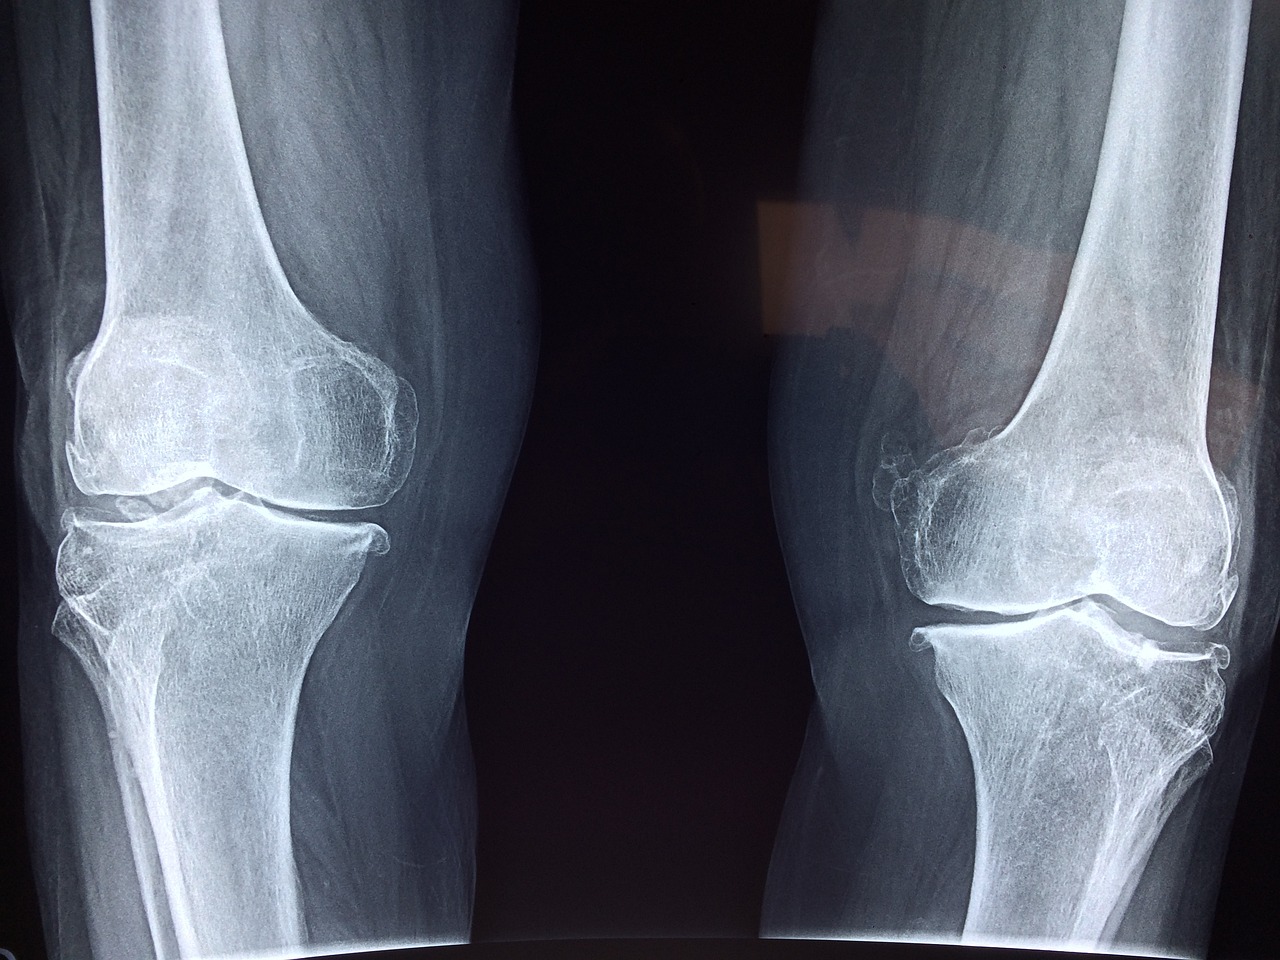

1. 퇴행성 관절염

퇴행성 관절염은 무릎 관절의 연골이 닳아 없어지면서 통증과 염증을 유발하는 질환입니다. 주로 노화로 인해 발생하지만, 비만이나 무리한 운동 등으로 인해 젊은 층에서도 나타날 수 있습니다. 계단을 오르내릴 때 통증이 심해지는 경향이 있습니다.